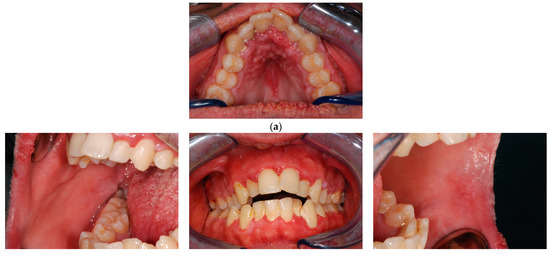

Clinical examination

At oral examination, multiple warty lumps were observed involving mainly the gingiva. The most affected area was the lower gingiva at the anterior portion. Of note, the attached gingiva of the central incisors had the typical cobblestone appearance. While the other mucous were free from lesions at the time of the first visit (Figure 4).

Figure 4.

Patient 3, clinical lesions. (a) Overall view. (b,c) Gingival lumps details.